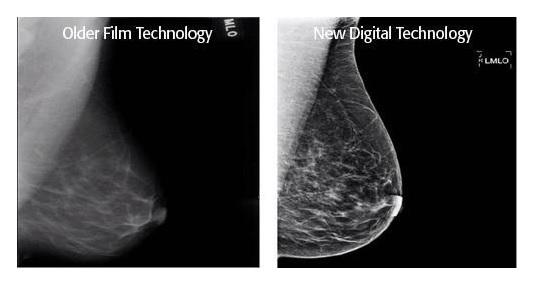

4. Not all mammograms are created equal

If you canm try to schedule and an appointment where they offer either breast tomosynthesis (3D mammograms) or spectral mammograms. For those of you who don't know, tomosynthesis is where the top part of the mammography machine moves over the cassette and takes multiple pictures and make a 3D image. Spectral mammography is where they inject a radioabsorbant dye into your bloodstram so it allows the radiaologist to better view the "vascular structure" of the breast. Both of these rival MRIs in sensitivity. If you can't get those, at the very least try to get a digital mammogram.